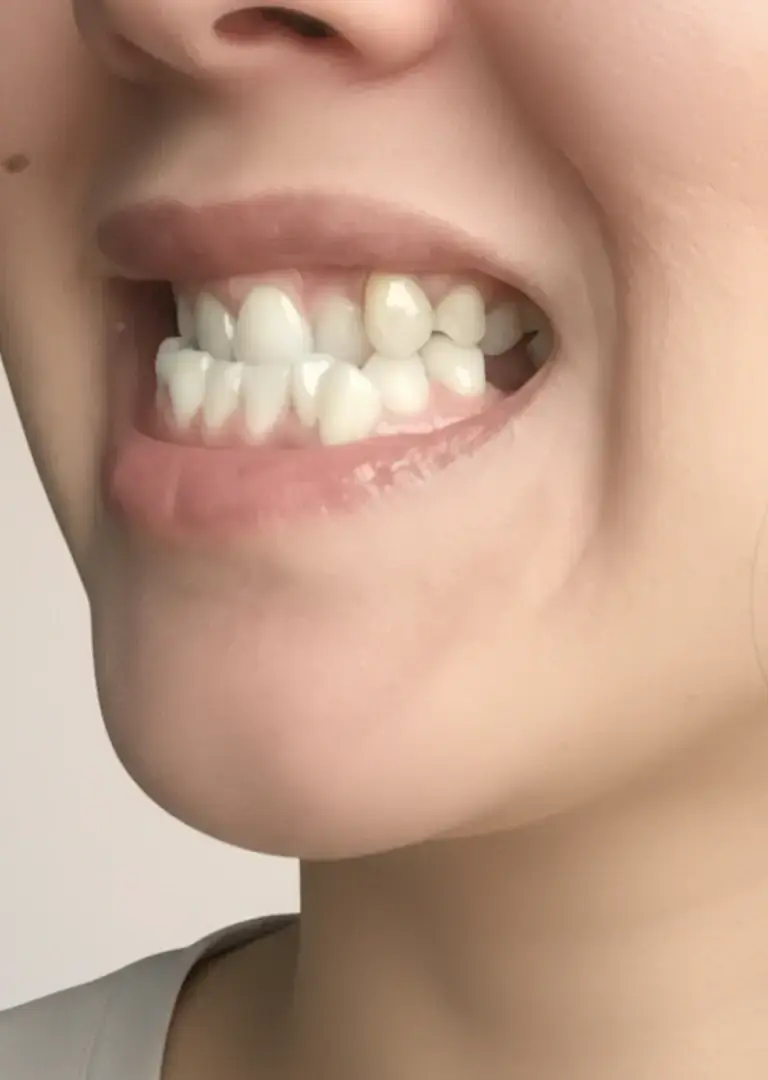

Мезиальный прикус у ребенка и взрослого: нижняя челюсть выдвинута вперед

Мезиальный прикус или прогения — аномалия, при которой нижняя челюсть и зубы выступают вперед относительно верхних. Со стороны лицо имеет «волевой» или «упрямый» профиль, так как нижняя треть лица визуально более массивная.

Симптомы мезиальной окклюзии: Вид сбоку: массивный, выступающий вперед подбородок. Нижние зубы перекрывают верхние, формируя так называемое обратное смыкание. Вид спереди: «вогнутый» профиль лица, западение верхней губы. Происходит нарушение контакта между передними зубами и появляются проблемы с откусыванием пищи.

мезиальный прикус

мезиальный прикус

мезиальный прикус